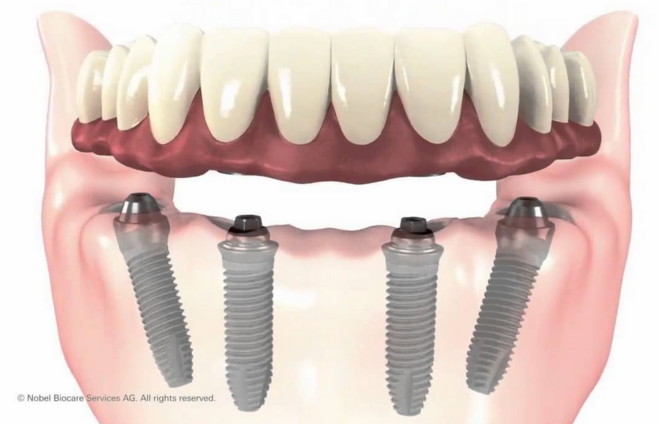

福利二、种植牙不再高不可攀

▲种植牙半价5折>>咨询

▲半口即刻用种植牙19999元 >>咨询

中老年种牙怕贵?怕疼?虽然种植牙被广泛赞誉,但仍有很多中老年人迟迟不敢选择。康贝佳即刻种植牙可以实现即刻种快速用,一颗牙5分钟就种好了,没有什么感觉。